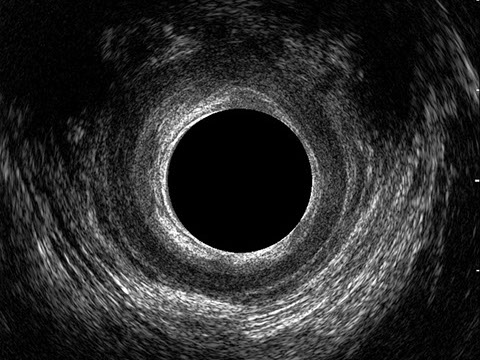

L’ecografia transanale è un esame diagnostico per immagini che consiste nell’introduzione di un trasduttore ad ultrasuoni. Le immagini qualitativamente migliori del canale anale sono ottenute usando un trasduttore rotante, montato in un manipolo rigido, che fornisce un’immagine a 360°. Con le apparecchiature più moderne è anche possibile ottenere immagini tridimensionali.

L’ecografia transanale permette di distinguere la sottomucosa che riveste il canale anale, lo sfintere anale interno, e lo sfintere anale esterno.

Le principali indicazioni all’esecuzione di tale esame sono lo studio dell’integrità delle strutture muscolari nei casi di incontinenza fecale, lo studio topografico dei processi settici perianali (ascessi e fistole) e lo studio dei processi proliferativi epiteliali (carcinoma anale).

Proctal dispone di apparecchiatura per ecografia endoanale 3D con sonda rotante.